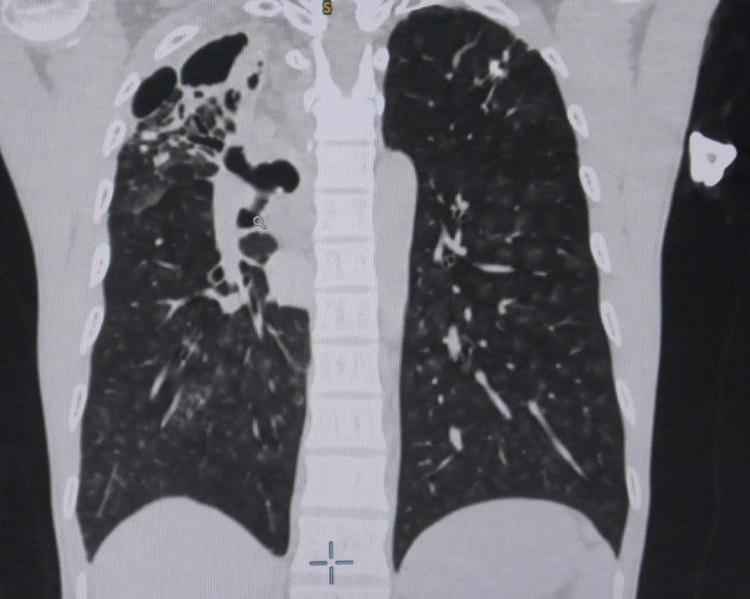

Tiếp nhận người bệnh tại khoa Cấp Cứu Bệnh viện Đa khoa Xuyên Á, các bác sĩ đã chỉ định cho anh H. nội soi phế quản, chụp CT ngực có thuốc cản quang để đánh giá tình trạng bệnh lý phổi. Kết quả ghi nhận phổi bên phải của anh H. có tình trạng hang lao cũ và có nhiều tổn thương giãn phế quản, phì đại động mạch phế quản.

Hình ảnh CT phổi cho thấy bệnh nhân bị vỡ mạch máu phế quản - Ảnh BVCC

Đây là nguyên nhân của tình trạng vỡ mạch máu phế quản – một bệnh lý nguy hiểm có thể gây suy hô hấp dẫn đến đe dọa tính mạng, thậm chí khi máu tràn vào đường thở, bệnh nhân có thể ngạt thở ngay lập tức, chưa kể mất máu nhanh chóng.